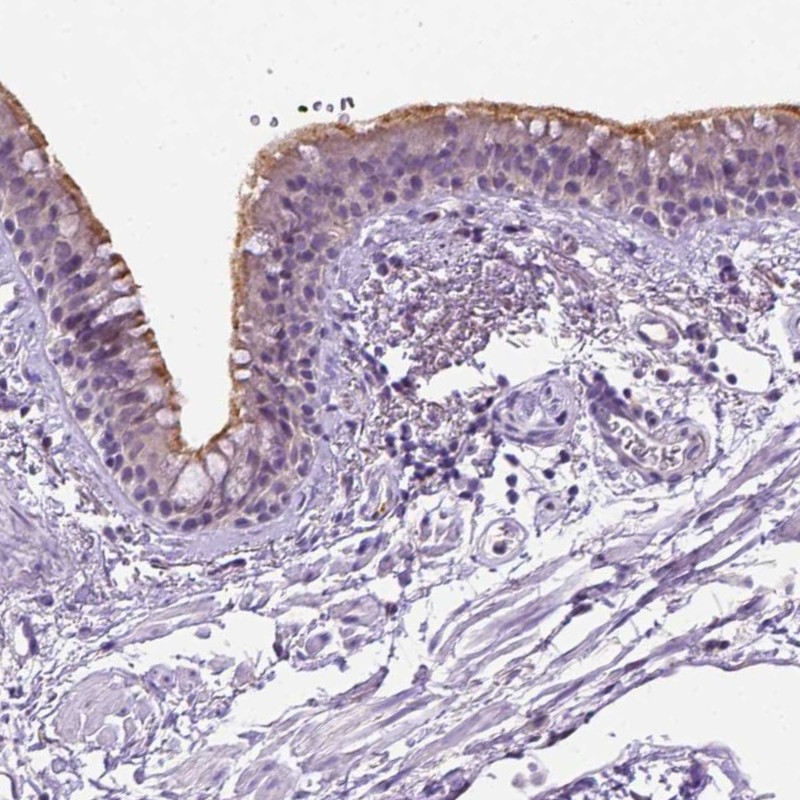

Immunohistochemical staining of human bronchus shows moderate positivity in cilia of respiratory epithelia cells.